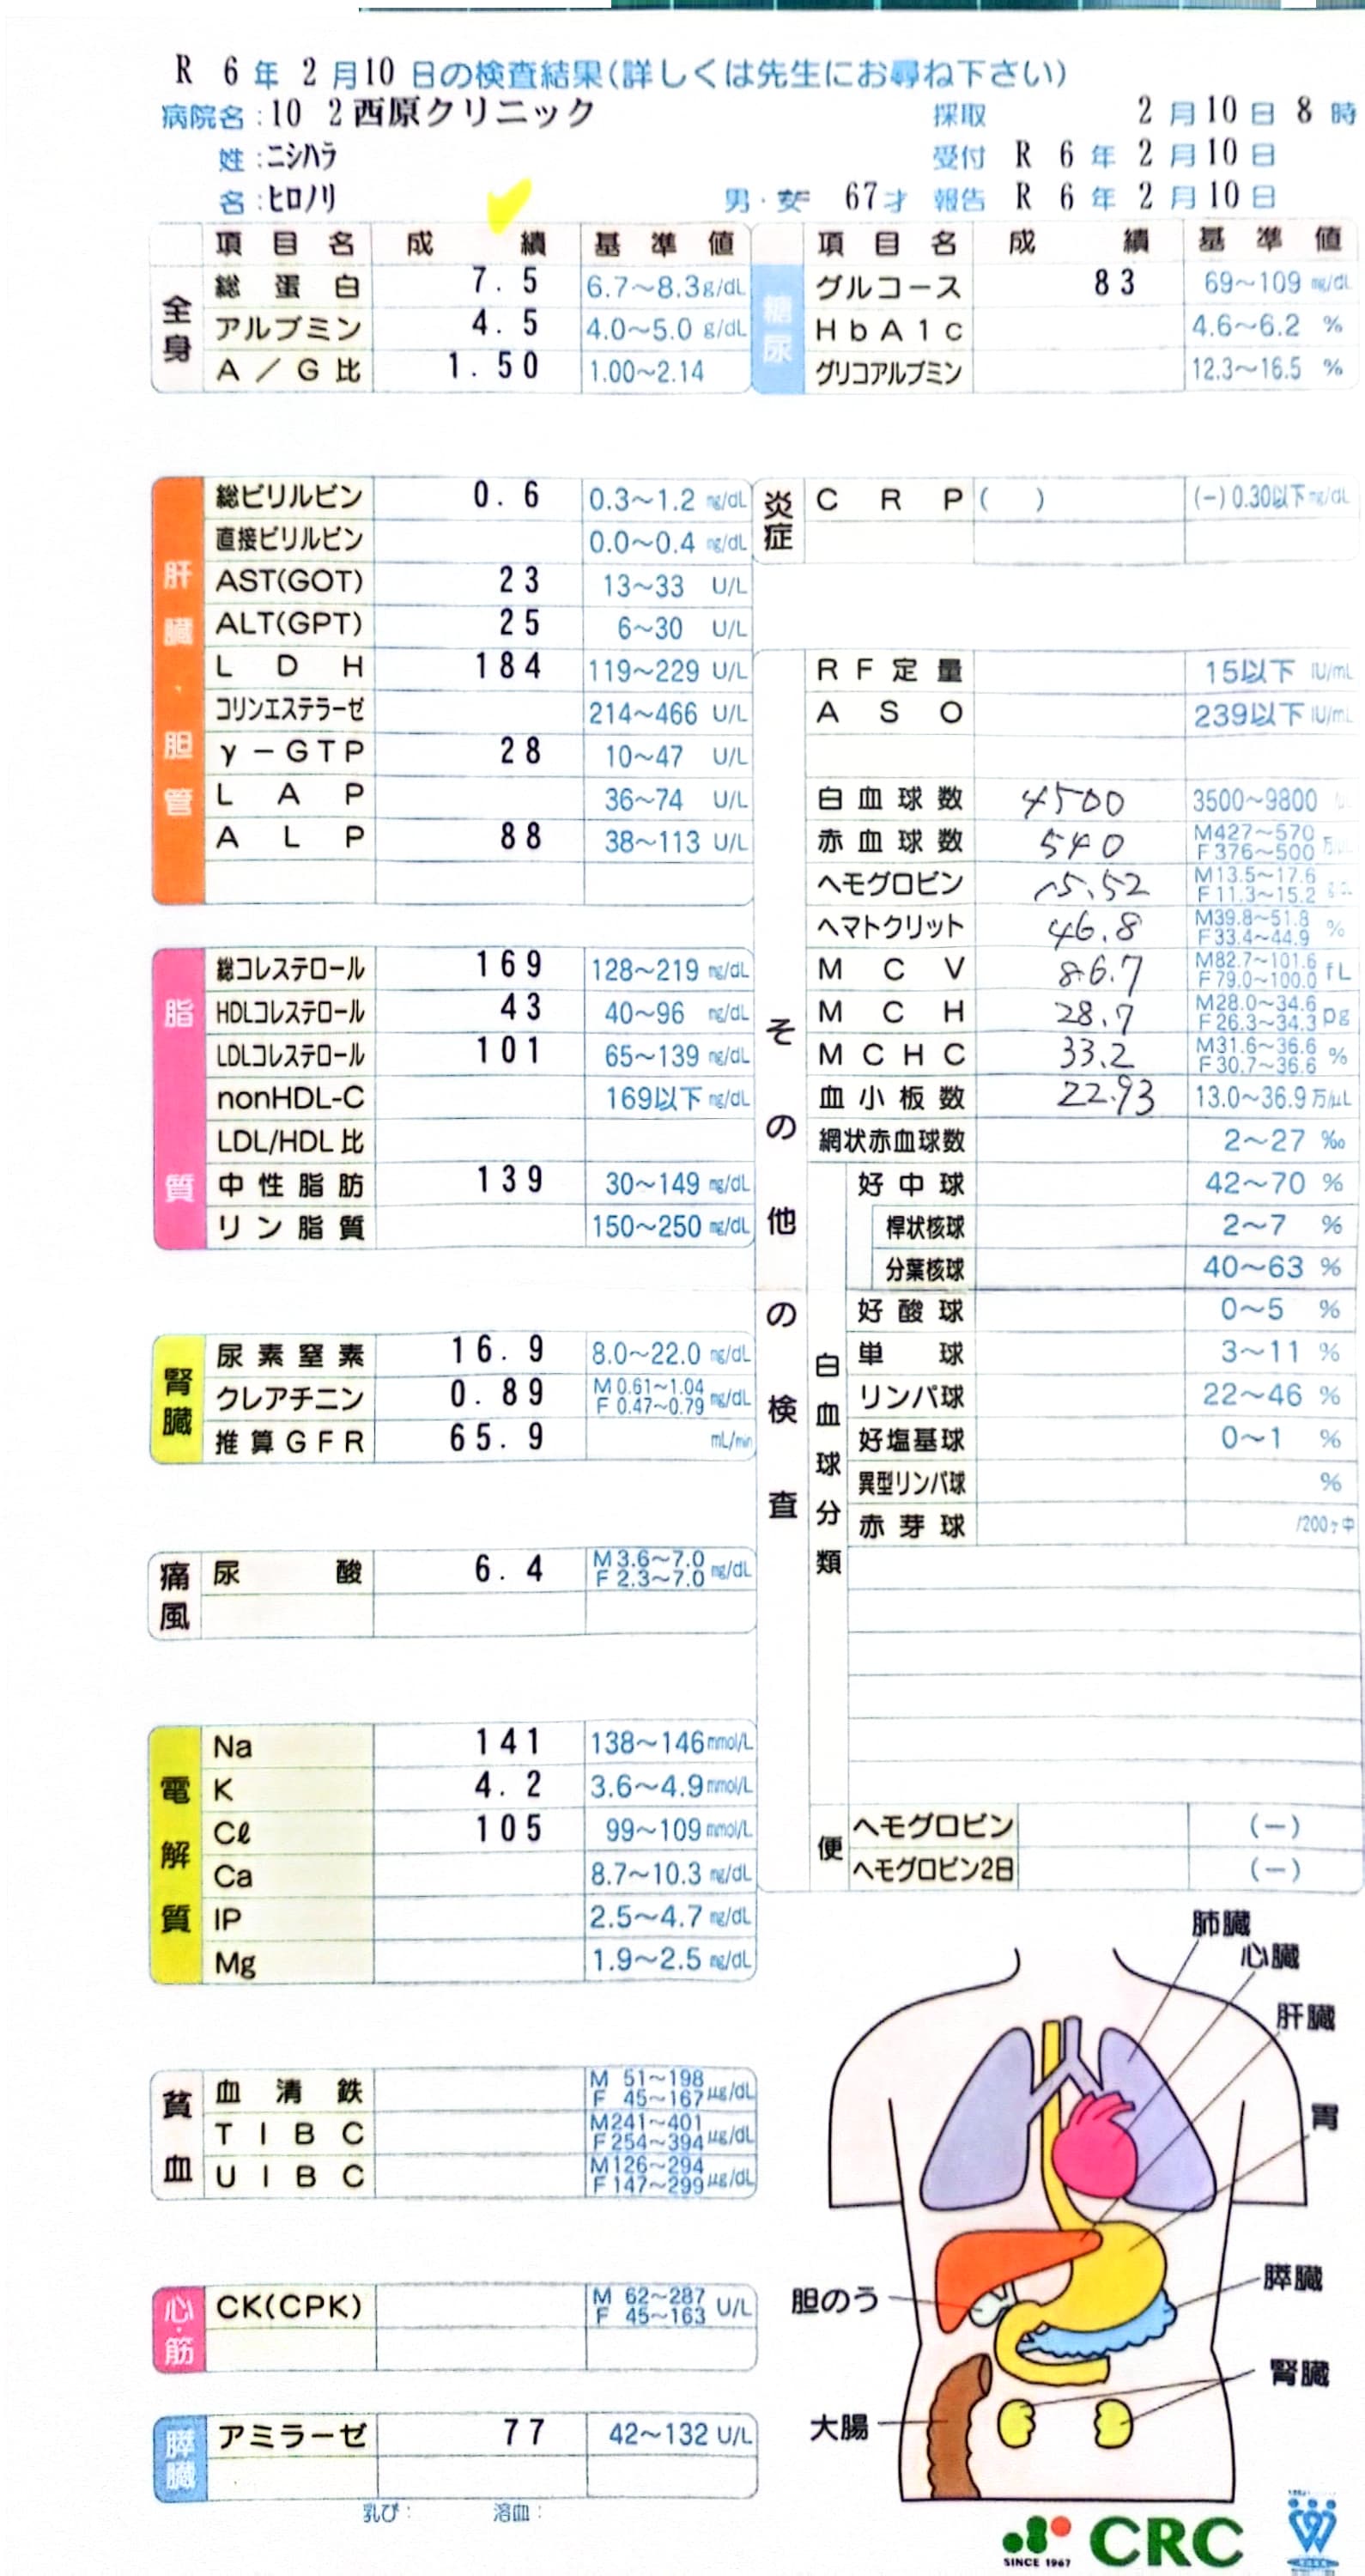

092 病院定期検査

2024-0210西原クリニック検査結果